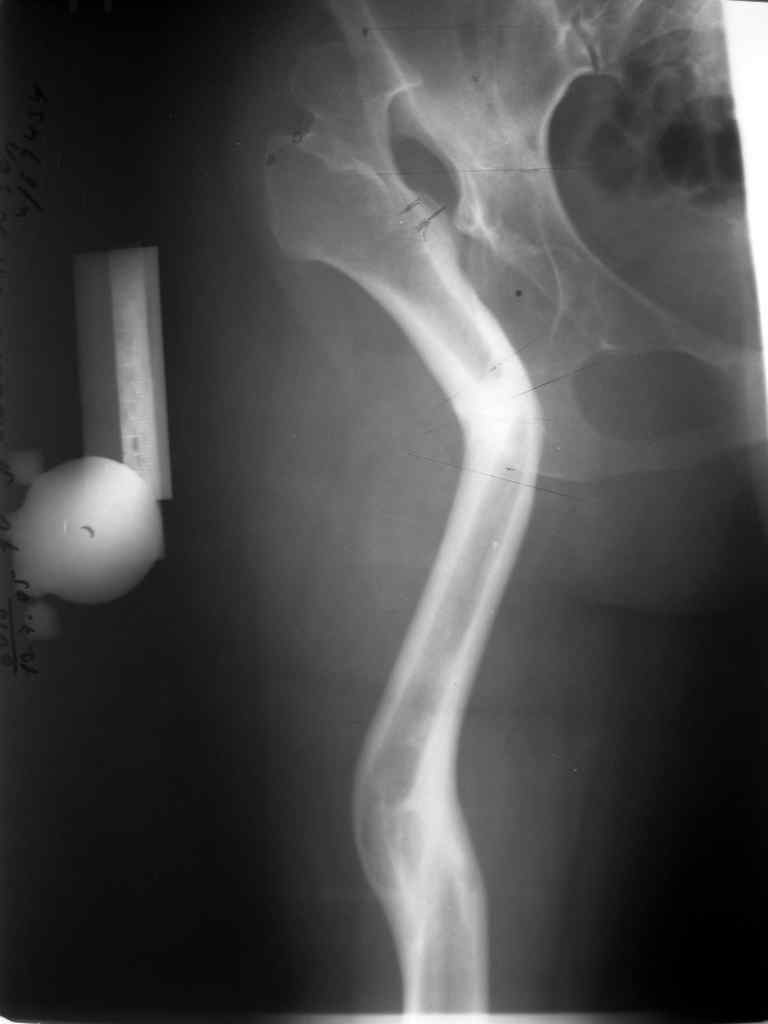

Слайд 1

Слайд 2

Слайд 3

Слайд 4

Devushka predstavlennaya na snimke nachala s LLD 9 cm, valgus deformation of the tibia, huge Trendelenburg( vidno na snimke).

Seichas : no LLD ,no Trendelenburg, reasonable hip motion.A samoe glavnoe ei ne predstoit kaghdye 10-15 let delat revision THR.

Уважаемый коллега! Не смогла не присоединиться к дискуссии, так как она стала непосредственно касаться опорных остеотомий, разработанных и широко применявшихся в нашем Центре - РНЦ "ВТО" им. академика Г.А.Илизарова в 80-90 годы. Следует отметить, что демонстрируемые примеры выполнения опорных остеотомий свидетельствуют о "незнании" врачами технических особенностей их выполнения. Проксимальная остеотомия должна быть выполнена на меж- или подвертельном уровне, но никак не на границе верхней и средней трети бедра, не требуется также такое громадное отведение промежуточного фрагмента, а, следовательно, не нужен и такой противоразворот на дистракционном регенерате.

Симптом Тренделенбурга нивелируется в случае хорощего упора в таз бедренной кости. Для такого упора достаточно медиализации бедра на половину или треть спила диафиза или метадиафиза, в зависимости от уровня выполнения проксимальной остеотомии. Есть несложные биомеханические расчеты, как и где выполнять "точку опоры" (Волокитина Е.А., автореф. канд. дисс. 1998 г.) От таких низких остеотомий, как в примере из Израиля, с огромным отведением и противоразворотом диафиза у нас уже давно отказались, начиная с работ Кадыкало, Куртова, Волокитиной. Первый опыт по опорыным остеотомиям обобщен в диссертации Терещенко В.А. (1981г.), потом уже низких опорных остеотомий уже не делали. Поэтому результаты нашего Центра достаточно хорошие: до 15-20 лет сохранятся движения, нет хромоты. В настоящий момент, спустя 20 лет после массового выполнения опорных остеотомий, стали появляться больные с жалобами на хромоту из-за появившегося болевого синдрома, кроме того, движения тоже с годами ограничиваются. Выполняем им эндопротезирование - сложно, тяжело, но эффект восстановления движений пациентов радует. Примеры клинические приводила в сборнике "Эдопротезировании в России" (ред. И.Ф.Ахтямов) за прошлый год, представляли доклады на форуме "Человек и здоровье", в Канаде на форуме франкоговорящих ортопедов. Интерес к нашим сообщениям огромный, не только в плане как после опорных остеотомий выполнять эндопротезирование, но и по самой методике опорных остеотомий типа Шнаца-Илизарова, которая остается актуальной для определенной группы больных и в наши дни.